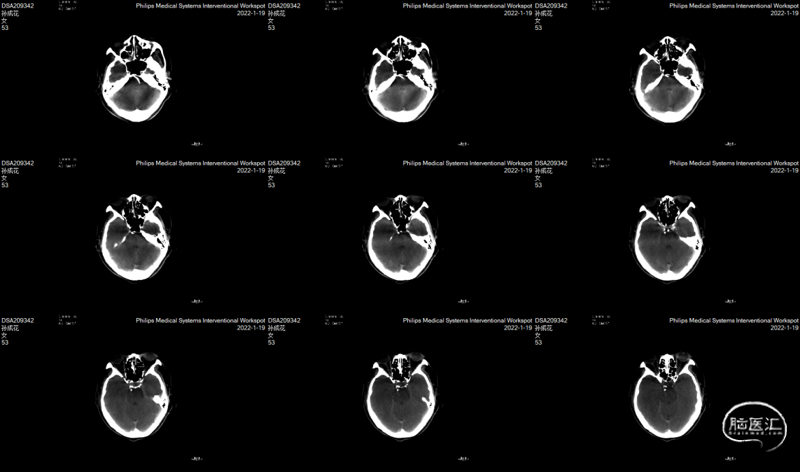

DSA(2022-01-19):

L-ICA

L-VA

R-ICA

复查DSA:左侧椎动脉V4段重度狭窄。

术中DynaCT。

术后4h CT。